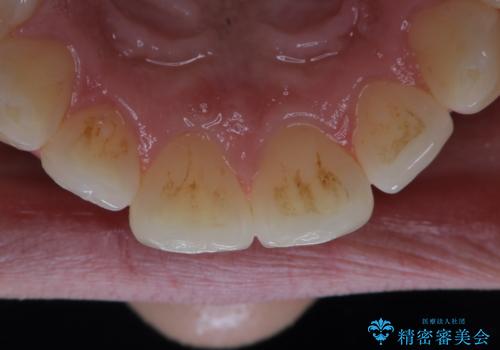

タバコによるヤニ、着色、歯の汚れをPMTC(60分コース)で除去。